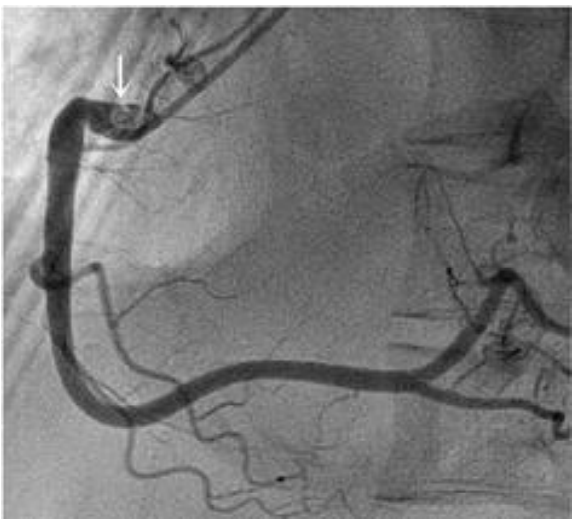

Mulher de 68 anos, com hipertensão e dislipidemia, foi atendida na emergência devido à dor torácica com 90 minutos de evolução. O

eletrocardiograma de admissão foi compatível com uma síndrome coronariana aguda com supradesnível de ST de parede inferior.

Encaminhada imediatamente à hemodinâmica e submetida à angioplastia com implante de stent no segmento proximal da coronária

direita com sucesso. Houve resolução da dor e do supradesnível do segmento ST, e não havia lesões residuais. Mantida dupla antiagregação

plaquetária, ao ser internada na unidade cardiointensiva seu eletrocardiograma revelou o traçado abaixo. No momento do registro a

paciente estava assintomática, com frequência cardíaca 70 bpm, pressão arterial 124x66 mmHg, e sem sinais de congestão pulmonar.